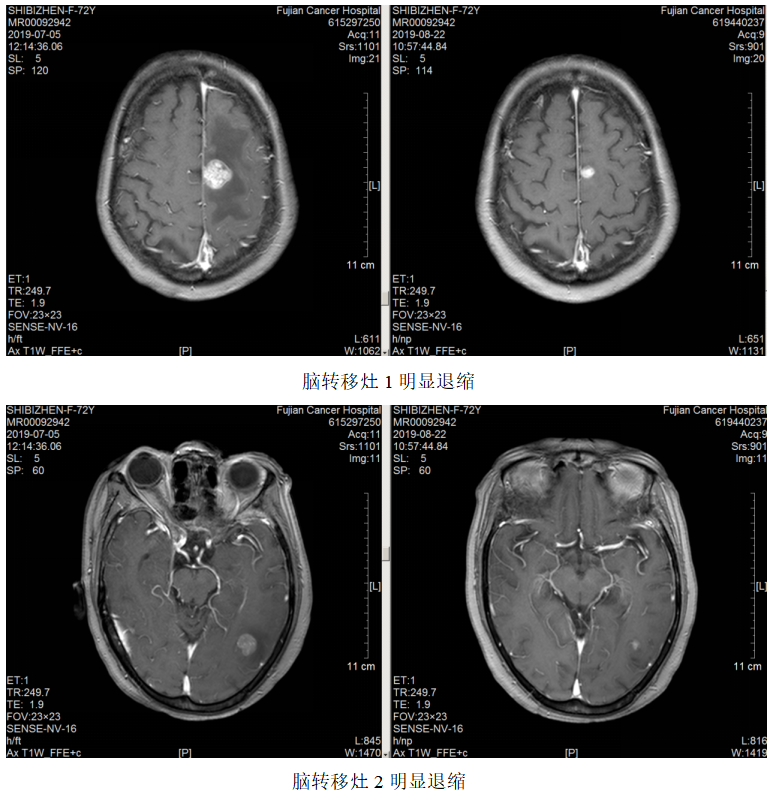

一线治疗:2019.7.12~10.24予FOLFOX方案(奥沙利铂110mg+左亚叶酸钙300mg+5-Fu 2.75)化疗8周期,曲妥珠单抗220mg靶向治疗7次。

局部放疗:2019.7.23~2019.8.7予脑转移灶调强放疗DT3900CGy/13F。

疗效评估:PR。

维持治疗:2019.11.6~2022.03.02予方案“卡培他滨+曲妥珠单抗q3w”维持治疗。